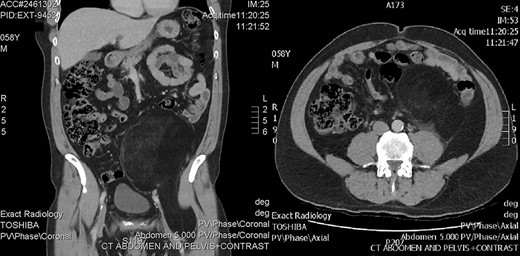

A 58-year-old male presented to his general practitioner with right scrotal swelling that developed over a week. He had an ultrasound followed by a computed tomography (CT) scan, which demonstrated a right hydrocoele, but also showed a well-defined lipomatous mass occupying much of the left side of the lower abdomen, extending from the edge of Gerota’s fascia behind the inguinal ligament towards the lesser trochanter. It was posterolateral to the external iliac artery and vein as they exited the pelvis. There was mild dilatation of the left upper ureter likely due to mass effect, but the left pararenal fat did not appear involved in the mass (Fig. 1). Subtle heterogeneity was noted on the scans which prompted a provisional diagnosis of well-differentiated liposarcoma (WDLS).